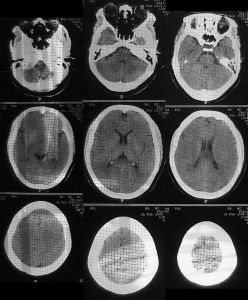

(2)cT掃描不僅可以直接顯示血腫大小和部位,還可以了解腦室受壓和中線結構移位的程度及並存的腦挫裂傷、腦水腫等情況,應及早套用於疑有顱內血腫患者的檢查。硬腦膜外血腫cT表現為顱骨內板與硬腦膜之間的雙凸鏡形或弓形高密度影;急性或亞急性硬腦膜下血腫cT表現為腦表面新月形高密度、混雜密度影,多伴有腦挫裂傷和腦受壓;腦內血腫表現為腦挫裂傷區附近或腦深部白質內類圓形或不規則高密度影。

顱內血腫--腦損傷即引起顱內壓增高,當顱內壓增高到一定程度可形成腦疝。根據血腫在腦內的位置不同可分為:硬腦膜外血腫、硬腦膜下血腫、腦內血腫。臨床以顱內高壓征為表現,診斷首先要明確出血的部位和出血量的多少,這對治療有指導意義。顱內血腫的治療效果與有無腦疝發生或腦幹受壓時間長短有密切關係。

有生命危險的患者,必須及時搶救,密切觀察病情變化,必要時及時請腦外科會診或轉科,千萬不可延誤搶救時機。嚴格掌握顱內血腫的開顱手術指征,一經確診儘快手術,開顱探查,清除血腫,徹底止血,減壓。中醫藥治療慢性硬腦膜下血腫較有影響的是20世紀70年代用顱內消瘀湯治療顱內血腫,用補陽還五湯加味治慢性硬腦膜下血腫,此外也有個案及少量中西醫結合綜合治療的臨床報告。以中醫為主治療這一病證難度大,但能體現中醫藥的長處。